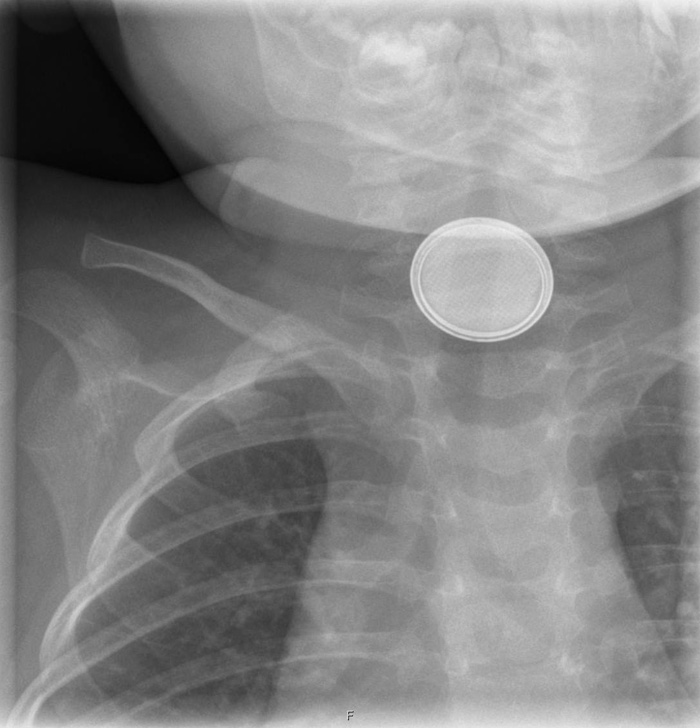

Det ble tatt røntgenbilde som viste et røntgentett fremmedlegeme forenlig med et 20 mm stort knappebatteri i øvre del av oesophagus.

Det er påvist at de sårbare slimhinnene i oesophagus kan nekrotisere allerede etter to timer. Årsaken til knappebatterienes store vevsnekrotiserende potensial er at det etableres en strømkrets (1). Risiko for skade er størst ved batteriets negative pol. Fryktede komplikasjoner er oesophagusperforasjon, mediastinitt og skade på omkringliggende strukturer. Røntgenbildet viser et røntgentett, rundt fremmedlegeme med halo. På et sidebilde vil man ved et slikt tilfelle kunne identifisere batteriets negative pol, som har mindre diameter og fremstår med et «step-off».